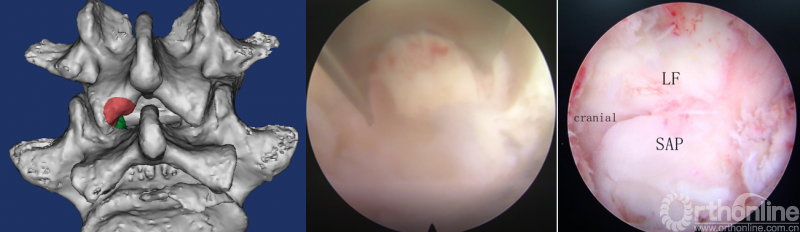

第三步“凿”:凿除部分下关节突,显露上关节突及黄韧带;

第四步“分”:分离上关节突及黄韧带;

第五步“咬”:咬除部分上关节突,显露椎间盘及神经根;